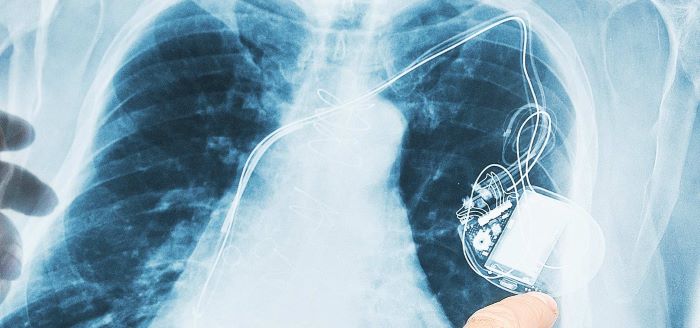

Pacemaker Leads

Thin insulated wires which transmit electrical impulses from the pacemaker to a particular chamber of the heart and communicate information about the activity of the heart back to the pacemaker.

The lead is made up of a metal alloy such as CoCrMo based alloy wires but is insulated by a polymer, such as polyurethane. The pacing leads generally have properties like ultra-high strength, toughness, ductility and excellent corrosion resistance. Depending on the pacemaker type, single or multiple-pacing leads can connect the chambers of the heart to the pacemaker.

Read more about smart pacemakers on our microsite on the Global Data platform.